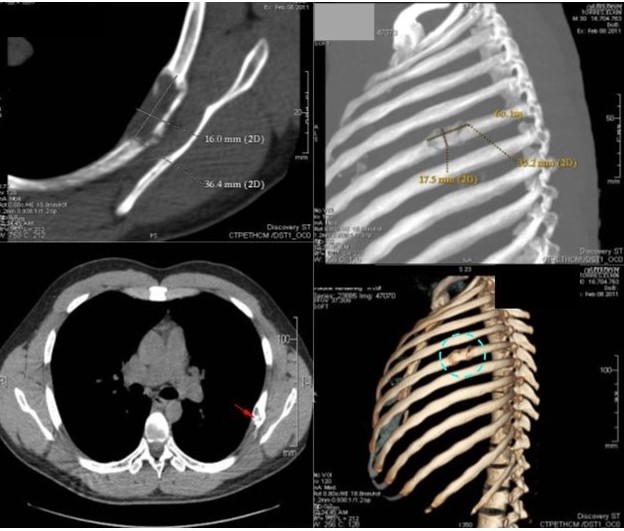

Paciente femenina de 26 años de edad, con antecedente patológico de carcinoma papilar de tiroides extirpado hace dos años, niega antecedentes familiares, es referida debido a que en un examen radiográfico posteroanterior de tórax, le detectan una radiopacidad a nivel del tercer (3er) arco costal posterior izquierdo, por lo cual fue remitida a la consulta externa de la Unidad de Cirugía de Tórax de nuestro centro hospitalario en donde es valorada. El examen físico y los exámenes de laboratorio dentro de parámetros normales. Por lo cual se indican exámenes clínico complementarios de laboratorio e imágenes (TC de tórax). Exámenes complementarios de laboratorio dentro de parámetro normales. Los estudios de imágenes como la radiografía simple de tórax posteroanterior y lateral, revelan una imagen radiopaca de apariencia redondeada, en forma de burbujas de jabón de unos 5 cm de diámetro, localizada a nivel del tercer (3er) arco costal posterior izquierdo (Figura 4).

En la TC de tórax con reconstrucción en 3D, se evidenció área radiolúcida en topografía de 3º arco costal posterior izquierdo con adelgazamiento y abombamiento de la cortical, de bordes bien definidos microlobulados que mide 5,0 cm x 4,5 cm, sin protrusión de dicha lesión hacia parénquima pulmonar y partes blandas dorsal compatible con lesión neoplásica benigna. Resto del plano óseo y blando sin evidencia de lesiones (Figura 5).